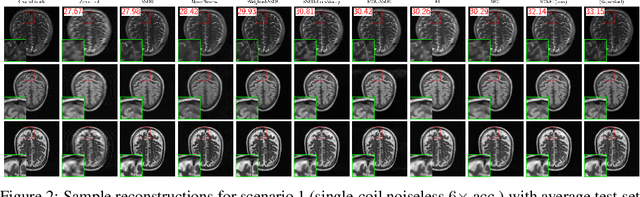

Abstract:Reconstructing MRI from highly undersampled measurements is crucial for accelerating medical imaging, but is challenging due to the ill-posedness of the inverse problem. While supervised deep learning approaches have shown remarkable success, they rely on fully-sampled ground truth data, which is often impractical or impossible to obtain. Recently, numerous self-supervised methods have emerged that do not require ground truth, however, the lack of systematic comparison and standard experimental setups have hindered research. We present the first comprehensive review of loss functions from all feedforward self-supervised methods and the first benchmark on accelerated MRI reconstruction without ground truth, showing that there is a wide range in performance across methods. In addition, we propose Multi-Operator Equivariant Imaging (MO-EI), a novel framework that builds on the imaging model considered in existing methods to outperform all state-of-the-art and approaches supervised performance. Finally, to facilitate reproducible benchmarking, we provide implementations of all methods in the DeepInverse library (https://deepinv.github.io) and easy-to-use demo code at https://andrewwango.github.io/deepinv-selfsup-fastmri.